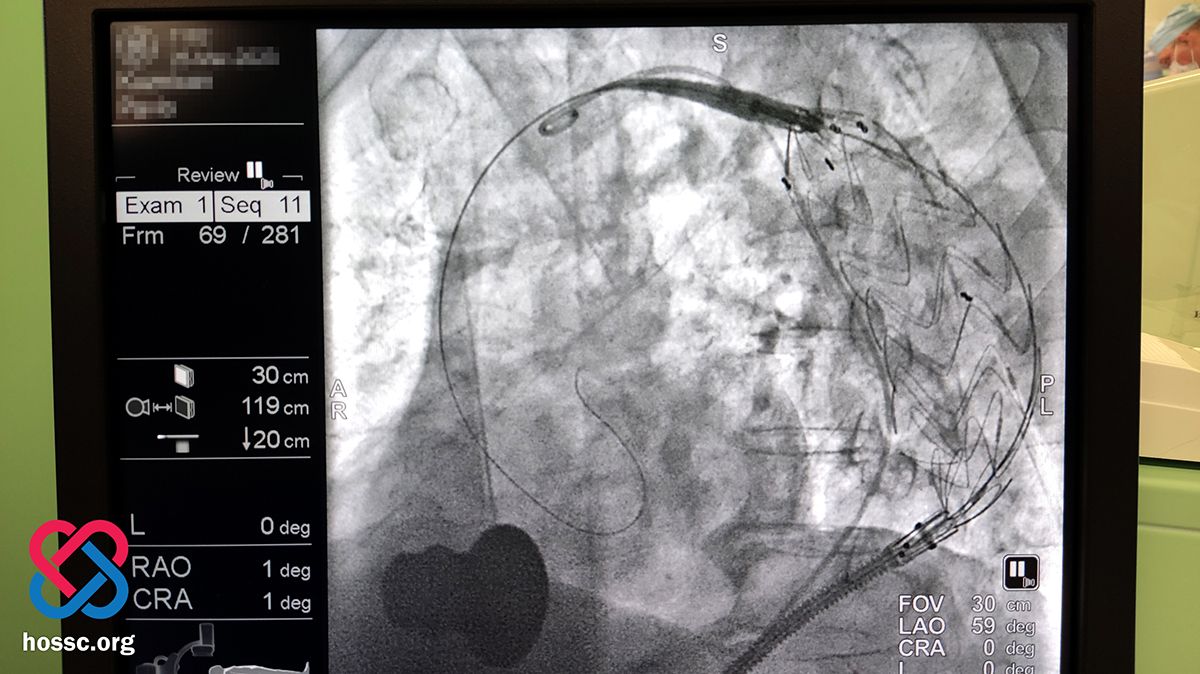

Нещодавно спеціалісти Хмельницького обласного серцево-судинного центру провели особливу операцію — торакальне ендоваскулярне протезування аорти. На сторінці медзакладу зазначають, що таке оперування зробили вперше на Хмельниччині.

Лікарі провели йому обстеження, комп’ютерну томографію, коронаро- та аортографію. Під час огляду вони помітили аневризму грудного та черевного відділу аорти з ознаками розшарування.

— З огляду на ураження судин, небезпеку ускладнень та загальний стан, пацієнту було заплановане та, в умовах катетеризаційної лабораторії виконане черезшкірне втручання – імплантація стент-графта у грудний відділ аорти, — пишуть лікарі.

Вони додають, що стент-графт — це внутрішньосудинний протез. Цей пристрій складається з підтримуючого каркасу з металевого сплаву (стента) і судинного ендопротеза (графта), виготовленого з тканого матеріалу. Після імплантації, стент-графт в розкритому стані максимально відповідає незміненій ділянці судини, до якої прилягає та укріплює її стінки.